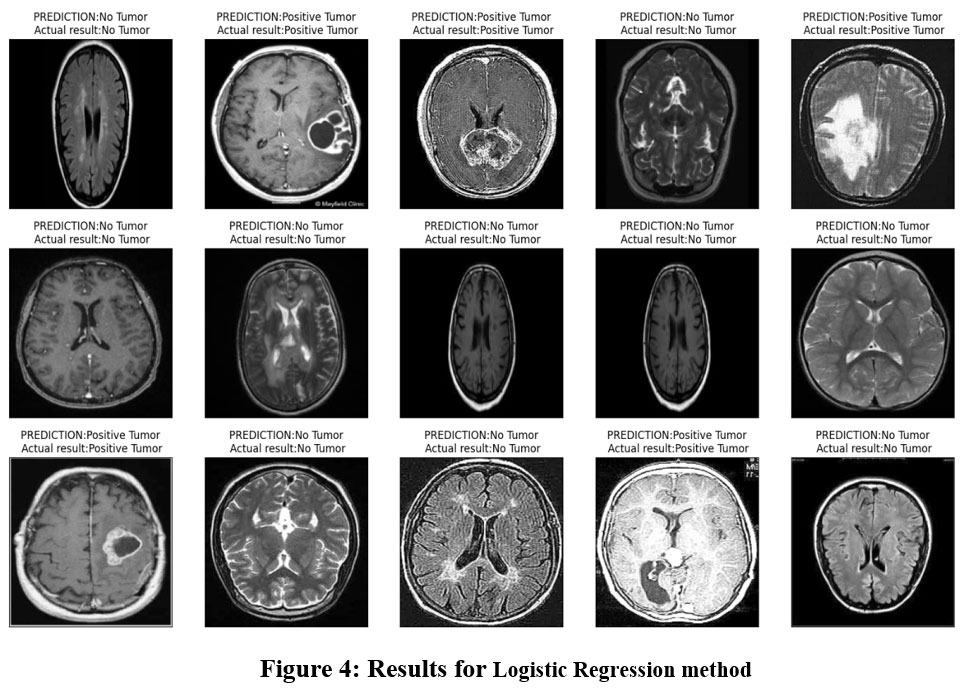

Figure 4: Results for Logistic Regression methodClick here to view Figure |

The performance of the Logistic Regression model is shown in the Table 1 such that it clearly exhibits the efficiency of the model for the brain tumor detection task. By applying the proposed model, it means that at 96% efficiency can accurately distinguish between tumor and non-tumor the cases in the given dataset. This not only indicates that the coefficients estimated under the Logistic regression model have rather significant coefficients, thus making the model rather accurate, but also that the model studies’ ability to correctly classify samples in the two classes is rather high. The reminder that the precision score is 0.96 enhances the already great realization that when the model predicts a brain tumor, it is right nearly all the time. Accuracy determines the rate of actual positive classification (correct detections of tumours) from all the positive classifications made by the model. When the model predicts a tumour then the likelihood is that the model is 96% correct, which is important in mostly medical related cases where false positives may lead to unnecessary diagnostics or treatment. The recall score of 0.97 just shows the proposed model can well classify the real brain tumor images. Sensitivity or the ability to recall refers to the ratio of actual tumor cases that the model has flagged correctly out of all actual tumor cases. The recall value of 0.97 also means that the model has the ability of identifying 97% of actual brain tumor cases and rarely compromising on the true negative rate which would potentially lead to an increase in false negatives, whereas many of the tumor cases as possible should be detected for further analysis or treatment.

This is a good approach because it gets a very high F1 score of 0.96, which means that it the model has the same recall and precision scores. Such a metric is the F1-score which is the harmonic mean of the precision and recall coefficients and offers a balance between the ability to correctly diagnose malignant tumor cases (seen through precision coefficient) and capture all possible cases of malignant tumors (seen through the recall coefficient). Thus, an F1-score of 0.96 demonstrates that proposed model is functioning equally to identify two aspects and thus, it could be used as a classifier model for brain tumor detection. Last of all, the AUC value of 0.96 shows that the proposed model is good in terms of the area under the curve. The AUC stands for the probability that the model will place a given positive example on higher rank than any randomly chosen negative one. An AUC of 0.96 reveals that the proposed solution – the Logistic Regression model – has a high potential to furnish distinguishable likelihood estimates of the imagery samples as brain tumor or non-tumor which is useful in avoiding possible false-positive or false-negative predictions that could potentially be fatal in clinical practice. All these performance measures indicate that the Logistic Regression model is quite accurate for the diagnosis of the brain tumor. Figure 4 demonstrate the prediction results of brain tumor for the given dataset using logical regression model and figure 5 shows the ROC and confusion matrix for linear regression model.